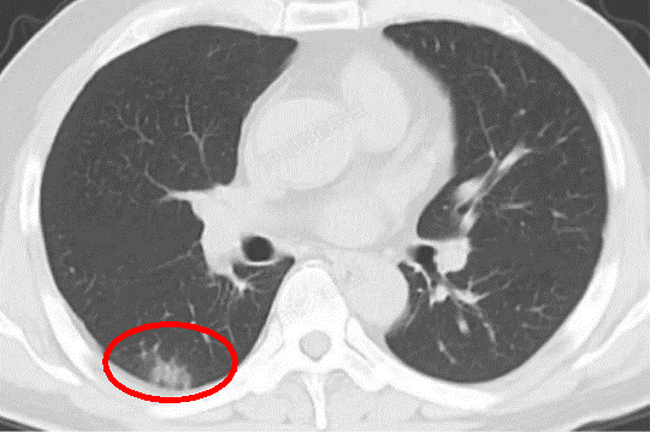

新冠病毒感染患者影像学特点早期多为肺外带小斑片影或间质改变,见图1:

▲ 图1

这是诊疗中常见的新冠病毒所致肺炎的CT表现,并不是“白肺”,那口语中的“白肺”的CT是什么样的(图2)?

只有肺部病变大于75%才是“白肺”,也就是白的面积大于整个肺部的75%。所以大多数仅仅是图1表现的,请放心,您目前不是“白肺”,只是肺有一点“白”。如果您年龄小于65岁,没有高危因素,只有干咳症状的话,而且症状逐渐减轻,那么您应该不会进展为“白肺”的。